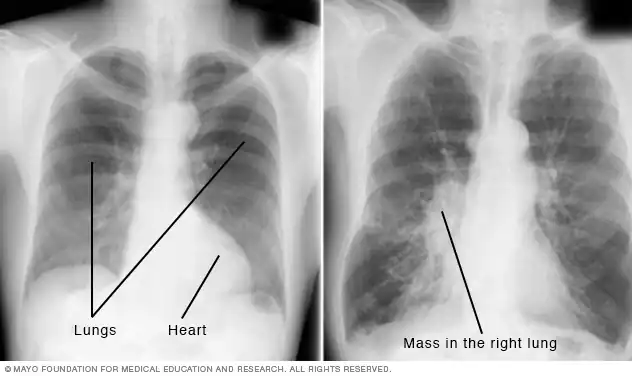

اشعه ایکس قفسه سینه

اشعه ایکس قفسه سینه به تشخیص مشکلات قلب و ریه کمک میکند. تصویر سمت چپ یک تصویر فرد معمولی است. تصویر سمت راست وجود یک توده در ریه راست را نشان میدهد.